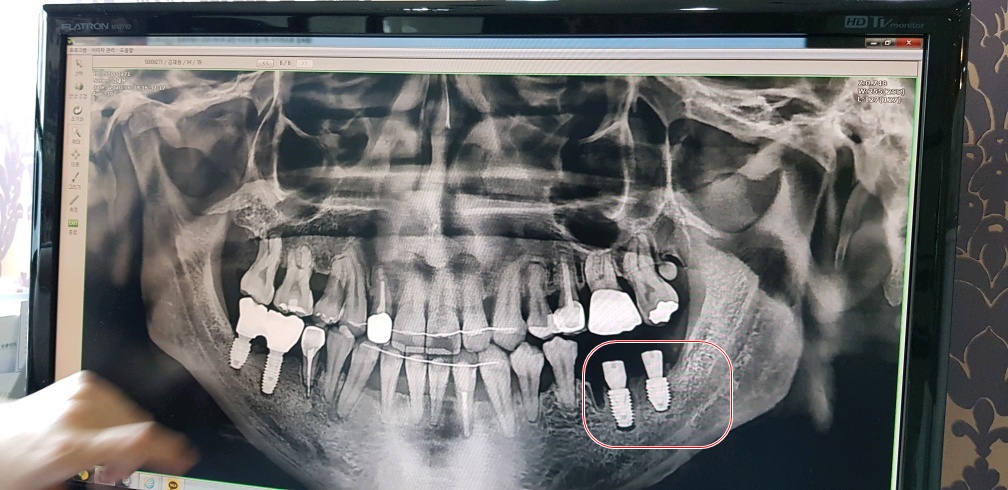

그렇게 30분 정도가 흐른 후 잘 박혔는지 엑스레이 찍고 후덜덜 한 상태로 드디어 끝났다...

잘심어진 건지는 모르겠으나.. 그냥 내가 겉보기엔 다행히도 잘 된거 같다..

근데 바로 앞의 치아뿌리가 왜저리 올라와 있는건지...;;

조만간에 저것도 해야된다고 하는거 아닌가 모르겠다 쩝..

그런데 임플란트는 두번째 문제였고 또하나의 더 큰 문제가 있었다.

여기 원장님 말로는 엑스레이 보여주면서

다른 교정치과에서 치료했던 치아가 문제인것 같다 한다..

신경치료 하면서 심어놨던 하얀색(치아뿌리의 중간부분)이 치아뿌리 안쪽에만 있어야 되는데

뿌리를 넘어서서 아픈것일 수도 있다고 하고(실제로 살짝 딱딱한걸 깨물어 보면 통증이 장난아니다..)

두번째로는 화살표 표시해둔 부분 이부분이 치아뿌리 끝 부터 염증이 생겨서 아픈것 일수도 있다고 한다..